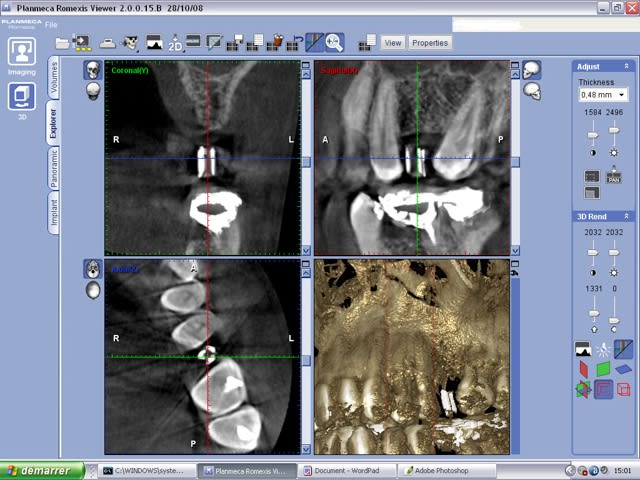

- d'autre part tu ne visualises sur le scanner que l'axe de ton forage et tu peux demander des coupes coronales obliques corrigées au radiologue... et ca c'est bcp plus important ! Je pourrais vous montrer de réelles différences entre 2 planches (corrigée et non corrigée).

je préfère avoir une dent radio opaque car l'image obtenue sur la radio me montre mon couloir prothétique ainsi que mon axe.

avec simplement de la gutta , tu ne vois que l'axe implantaire, pas les limites de mise en place de ton implant.